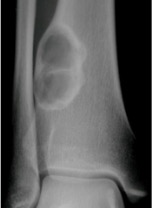

Giant cell tumour of distal tibia seen as eccentric expansile epiphyseal lucent lesion (arrows)

Giant cell tumour of bone

- Occur primarily in the mature skeleton

- Typical eccentric epiphyseal location, extending to subarticular surface

- Seen as radiolucent lesion with well-defined, but non-sclerotic, margin

- May be expansile with cortical thinning

- Approximately 15% of giant cell tumours are malignant